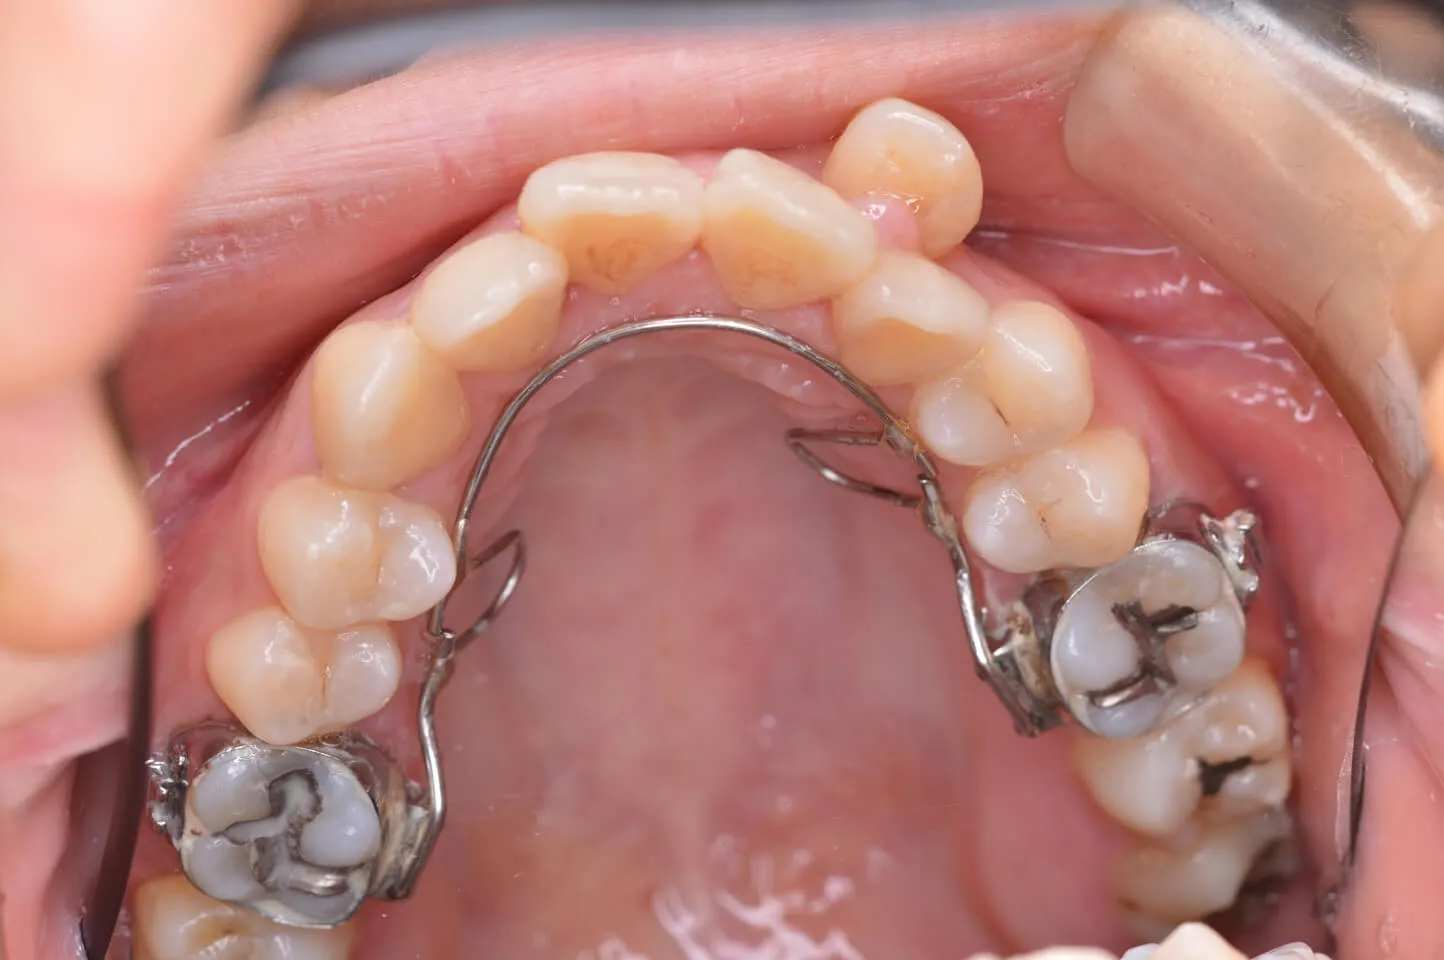

裏側の装置を装着しました。